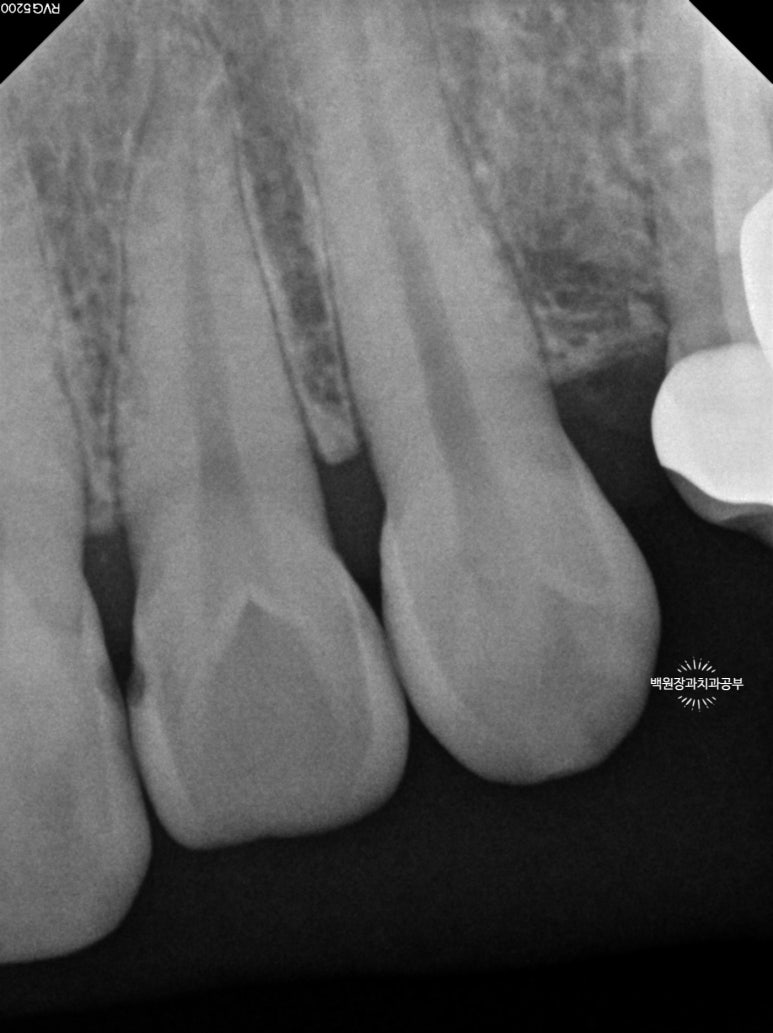

충치의 범위를 파악하기 위해 작은 엑스레이를 찍어봤어요.

Previous image Next image

총 세장의 치과용 치근단 방사선사진을 찍었고,

각 치아마다 옆면의 충치 범위를 확인할 수 있었어요!

까맣게 물들듯 보이는 곳들이 충기가 있는 곳입니다.

치과용 엑스레이 판독을 일반 사람이 하기는 힘드니깐,

제가 보기 쉽게 표시해 드릴께요!!

노란색으로 표시해 놓은 곳들이 옆면 충치가 있는 곳들이에요!

눈으로 확인하는 시진과 방사선 검사를 종합해서 합집합이 되는 부위를 모두 치료하면 됩니다.